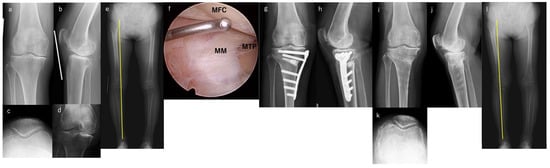

2. Materials and Methods

2.2. Perioperative Medication Management, Surgical Technique, and Postoperative Rehabilitation

3. Results

3.3. Radiographic Outcomes